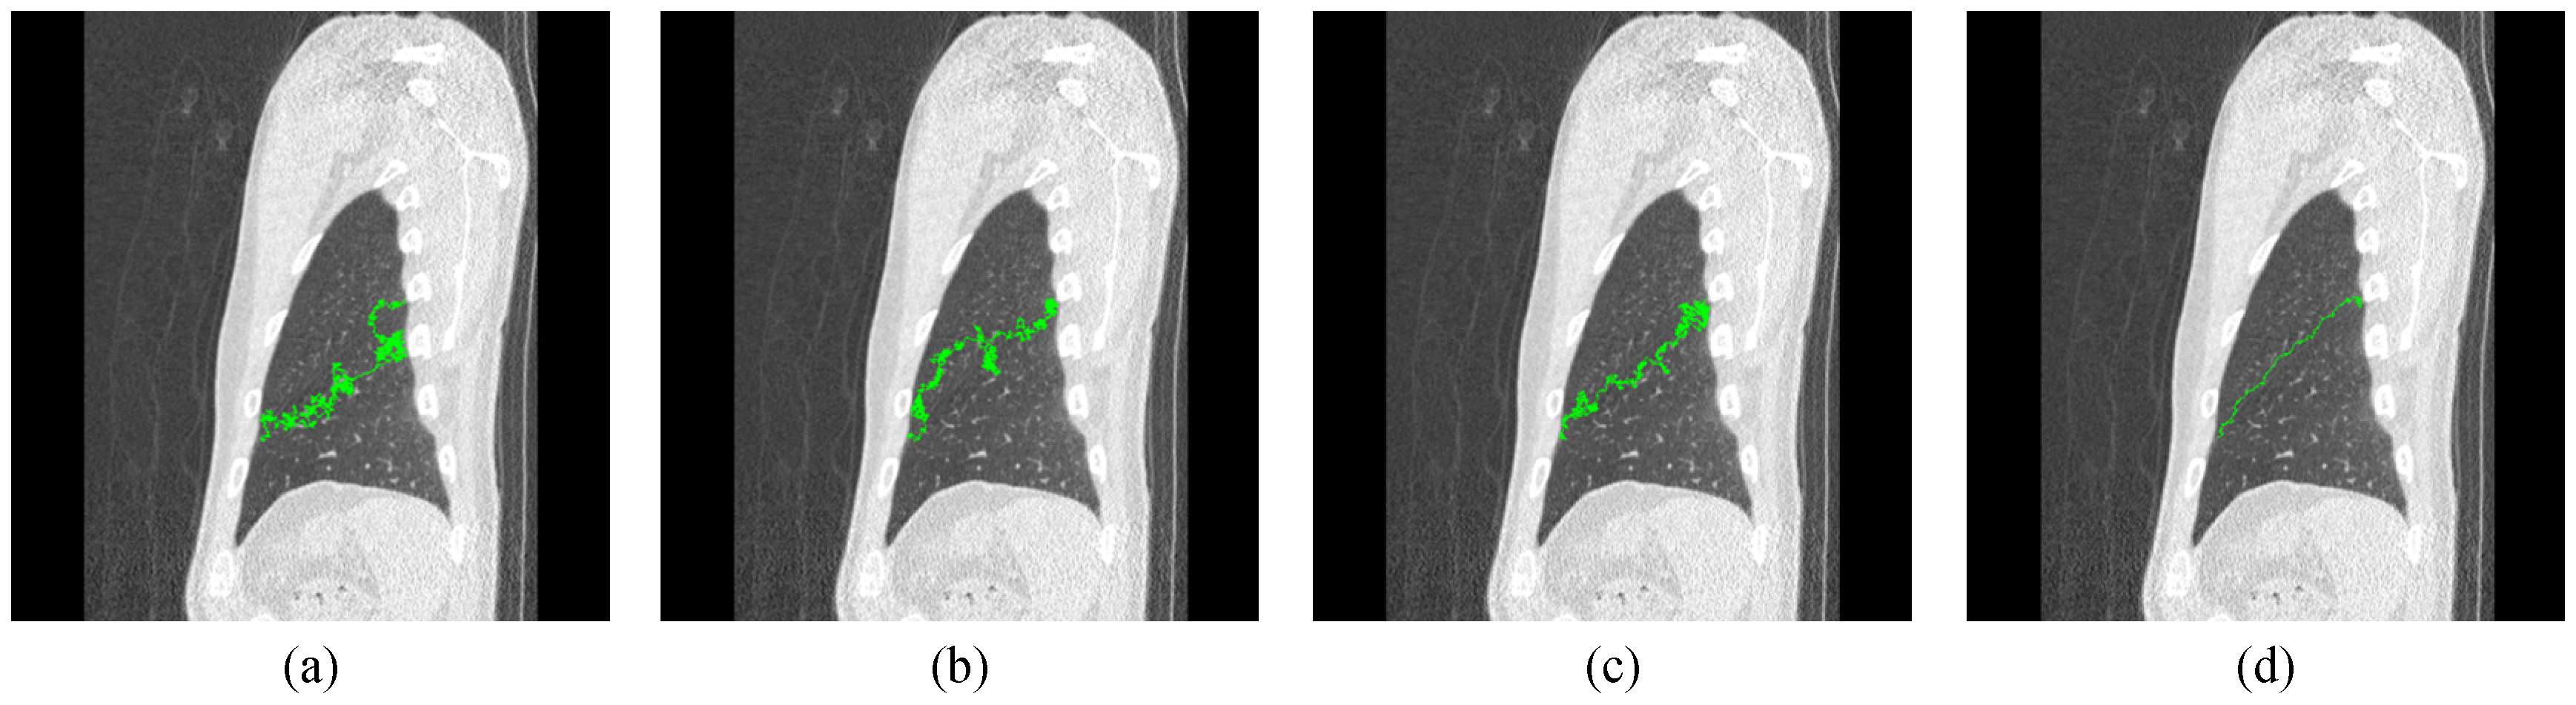

The Lobe Fissure Tracking by the Modified Ant Colony Optimization Framework in CT Images

2.1. Ant Colony Algorithm

3. Tracking Framework for Lobe Fissure Based on Modified ACO Algorithm

4. Experimental Results